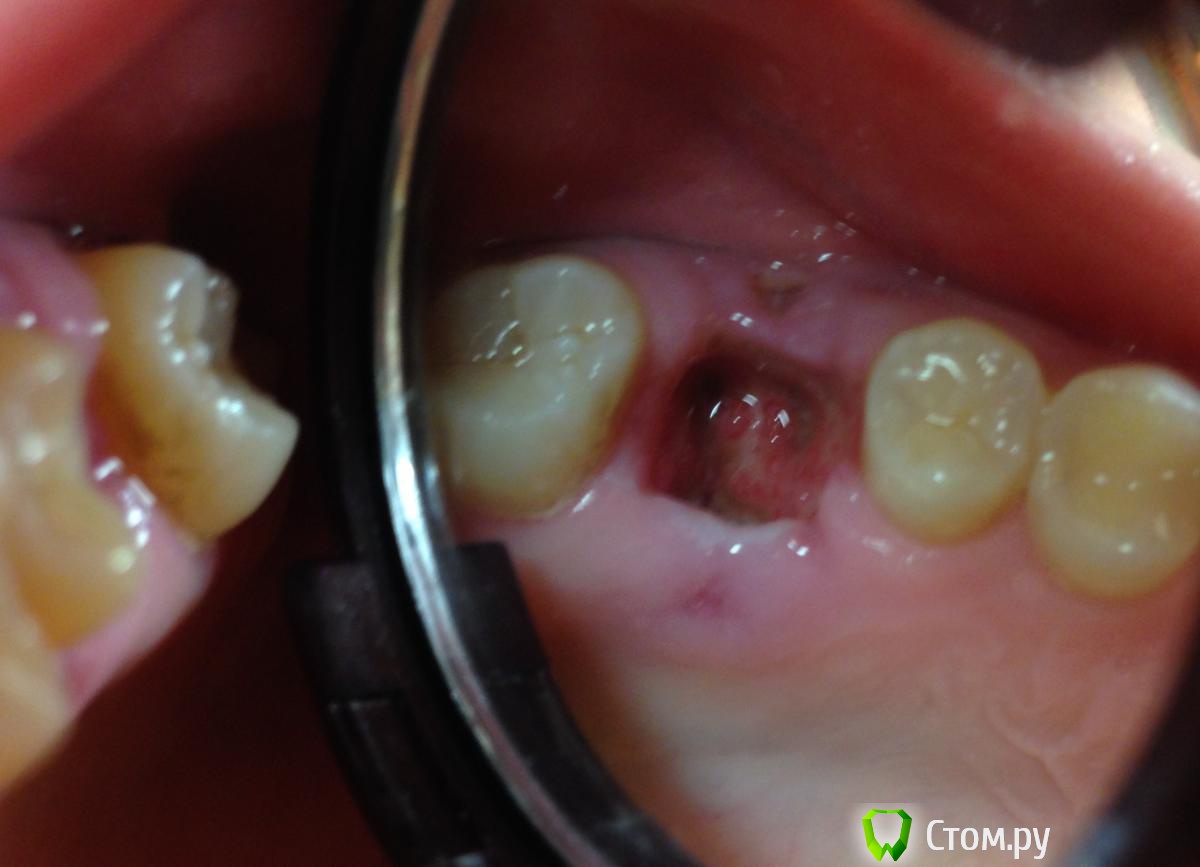

5 июня пошла к тому врачу, который удалял зуб. Сделал снимок - в десне небольшие остатки старого лечения каналов, сказал это нормально. Лунку прочистил, сказал сгустка нет, это просто забилась еда. При вычищении было жутко больно, снова пошла кровь. Никаких лекарств он при этом не применял. Назначил аккуратные полоскания с Тандум Верде и мазь Солкосерил.

С Солкосерилом стало намного легче, ибо дырка стала просто огроменной. Замазываю ее периодически, чаще перед едой. Температура 37

С момента удаления зуба прошло 9 дней. Солкосерил уже бесит, но без него еще хуже. Еще и дырка небольшая появилась в десне после зашивания, на фото видно. Все слишком плохо? Что делать дальше? Нужны ли физио процедуры, антибиотики, что-то еще?

post-39094-0-46871400-1402226530_thumb.jpg

По Вашим фото снимкам (предварительно)  кроме  " банального"  альвеолита ничего на ум не приходит)